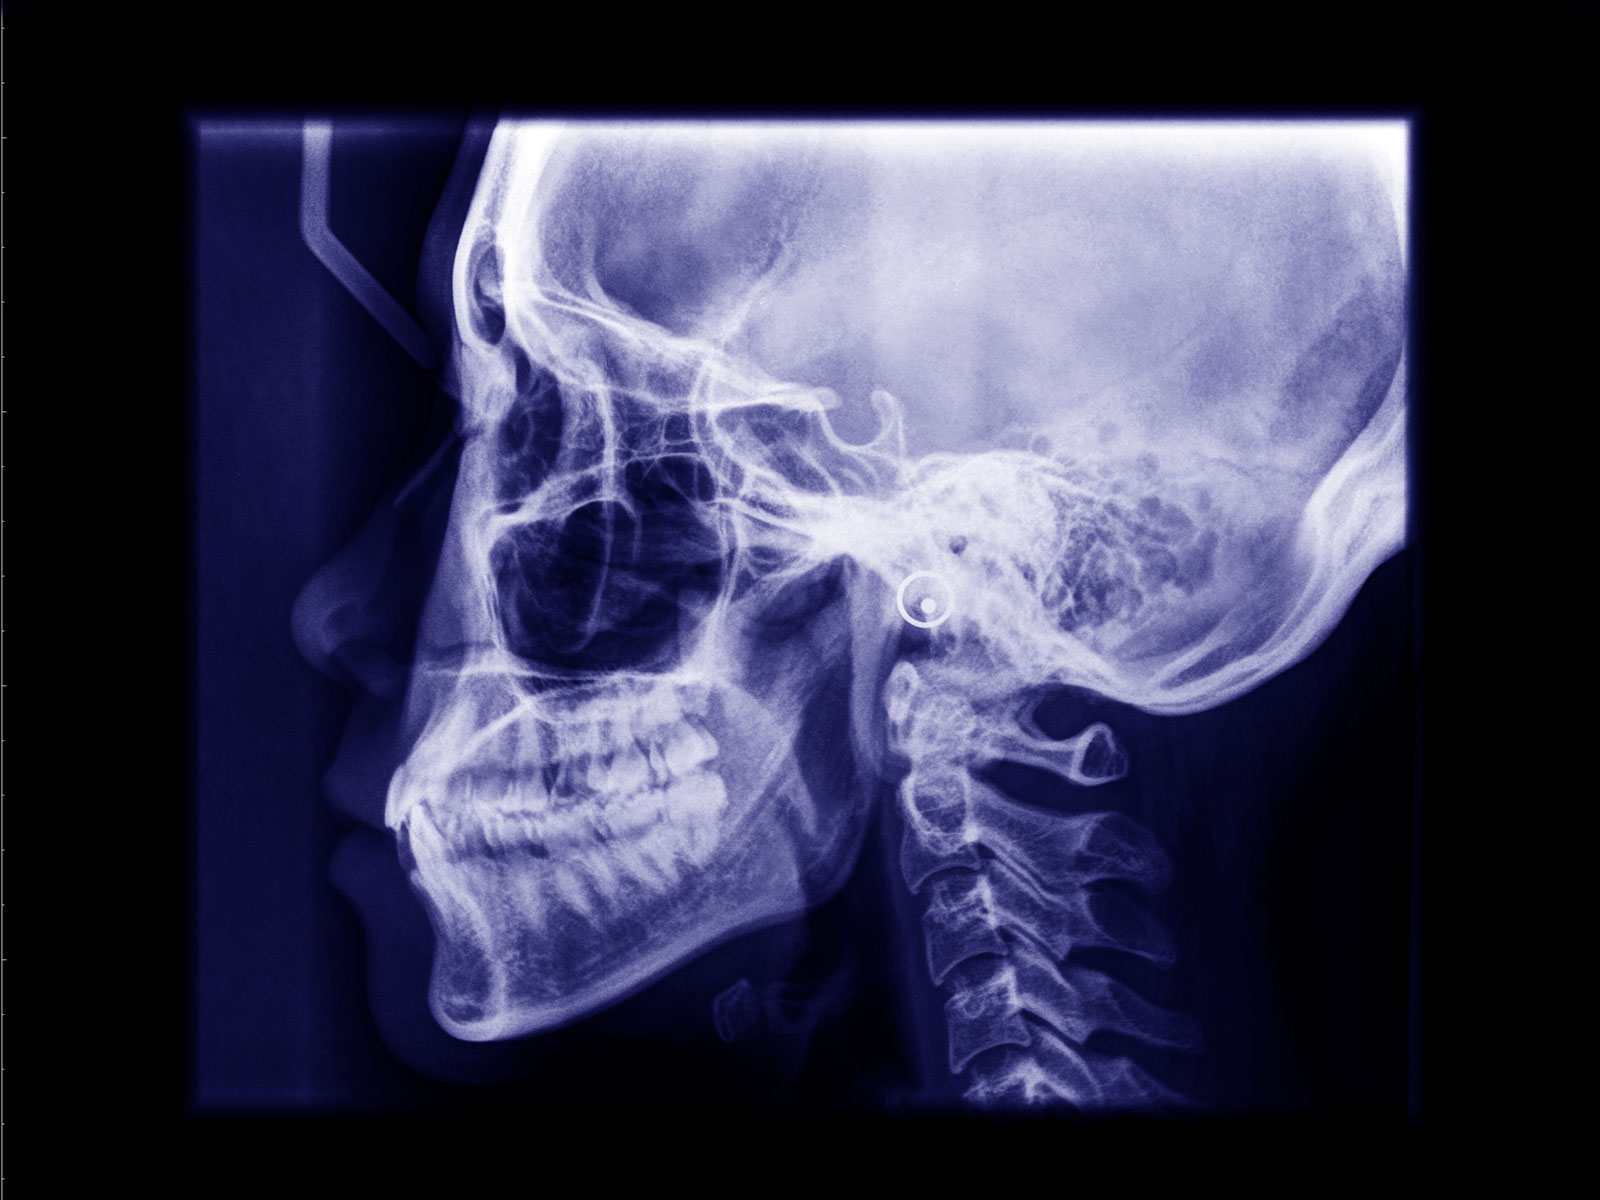

Orthognathic surgery involves the surgical manipulation to correct a wide range of minor problems with the jaw and facial structure caused by growth, sleep apnea, TMJ disorders, imperfect positioning of the teeth or other orthodontic problems that cannot be fixed with braces. Surgery can help improve a person’s speaking, chewing and breathing.